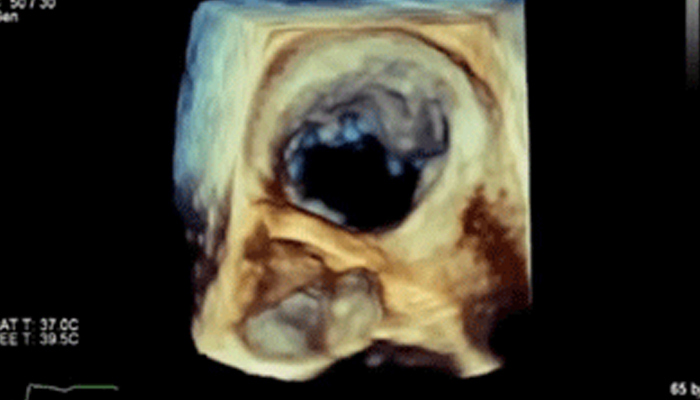

تشهد حاليًا خيارات العلاج التي لا تتطلب سوى تدخل جراحي محدود في القلب والأوعية الدموية انتشارًا ملحوظًا. ولقد ساهمت التطورات الأخيرة في مجالات التشخيص والتوجيه بالصور المباشرة Live Image Guidance والمعلوماتية في جعل هذا الأمر ممكنًا. بالتعاون مع أشهر أطباء أمراض القلب، ابتكرنا حلولاً تساهم في منح المرضى الفرصة لتغيير حياتهم. فهذه الحلول تساعد في تسريع سير العمل وزيادة فعالية الطاقم الطبي وتوفير أفكار سريرية.